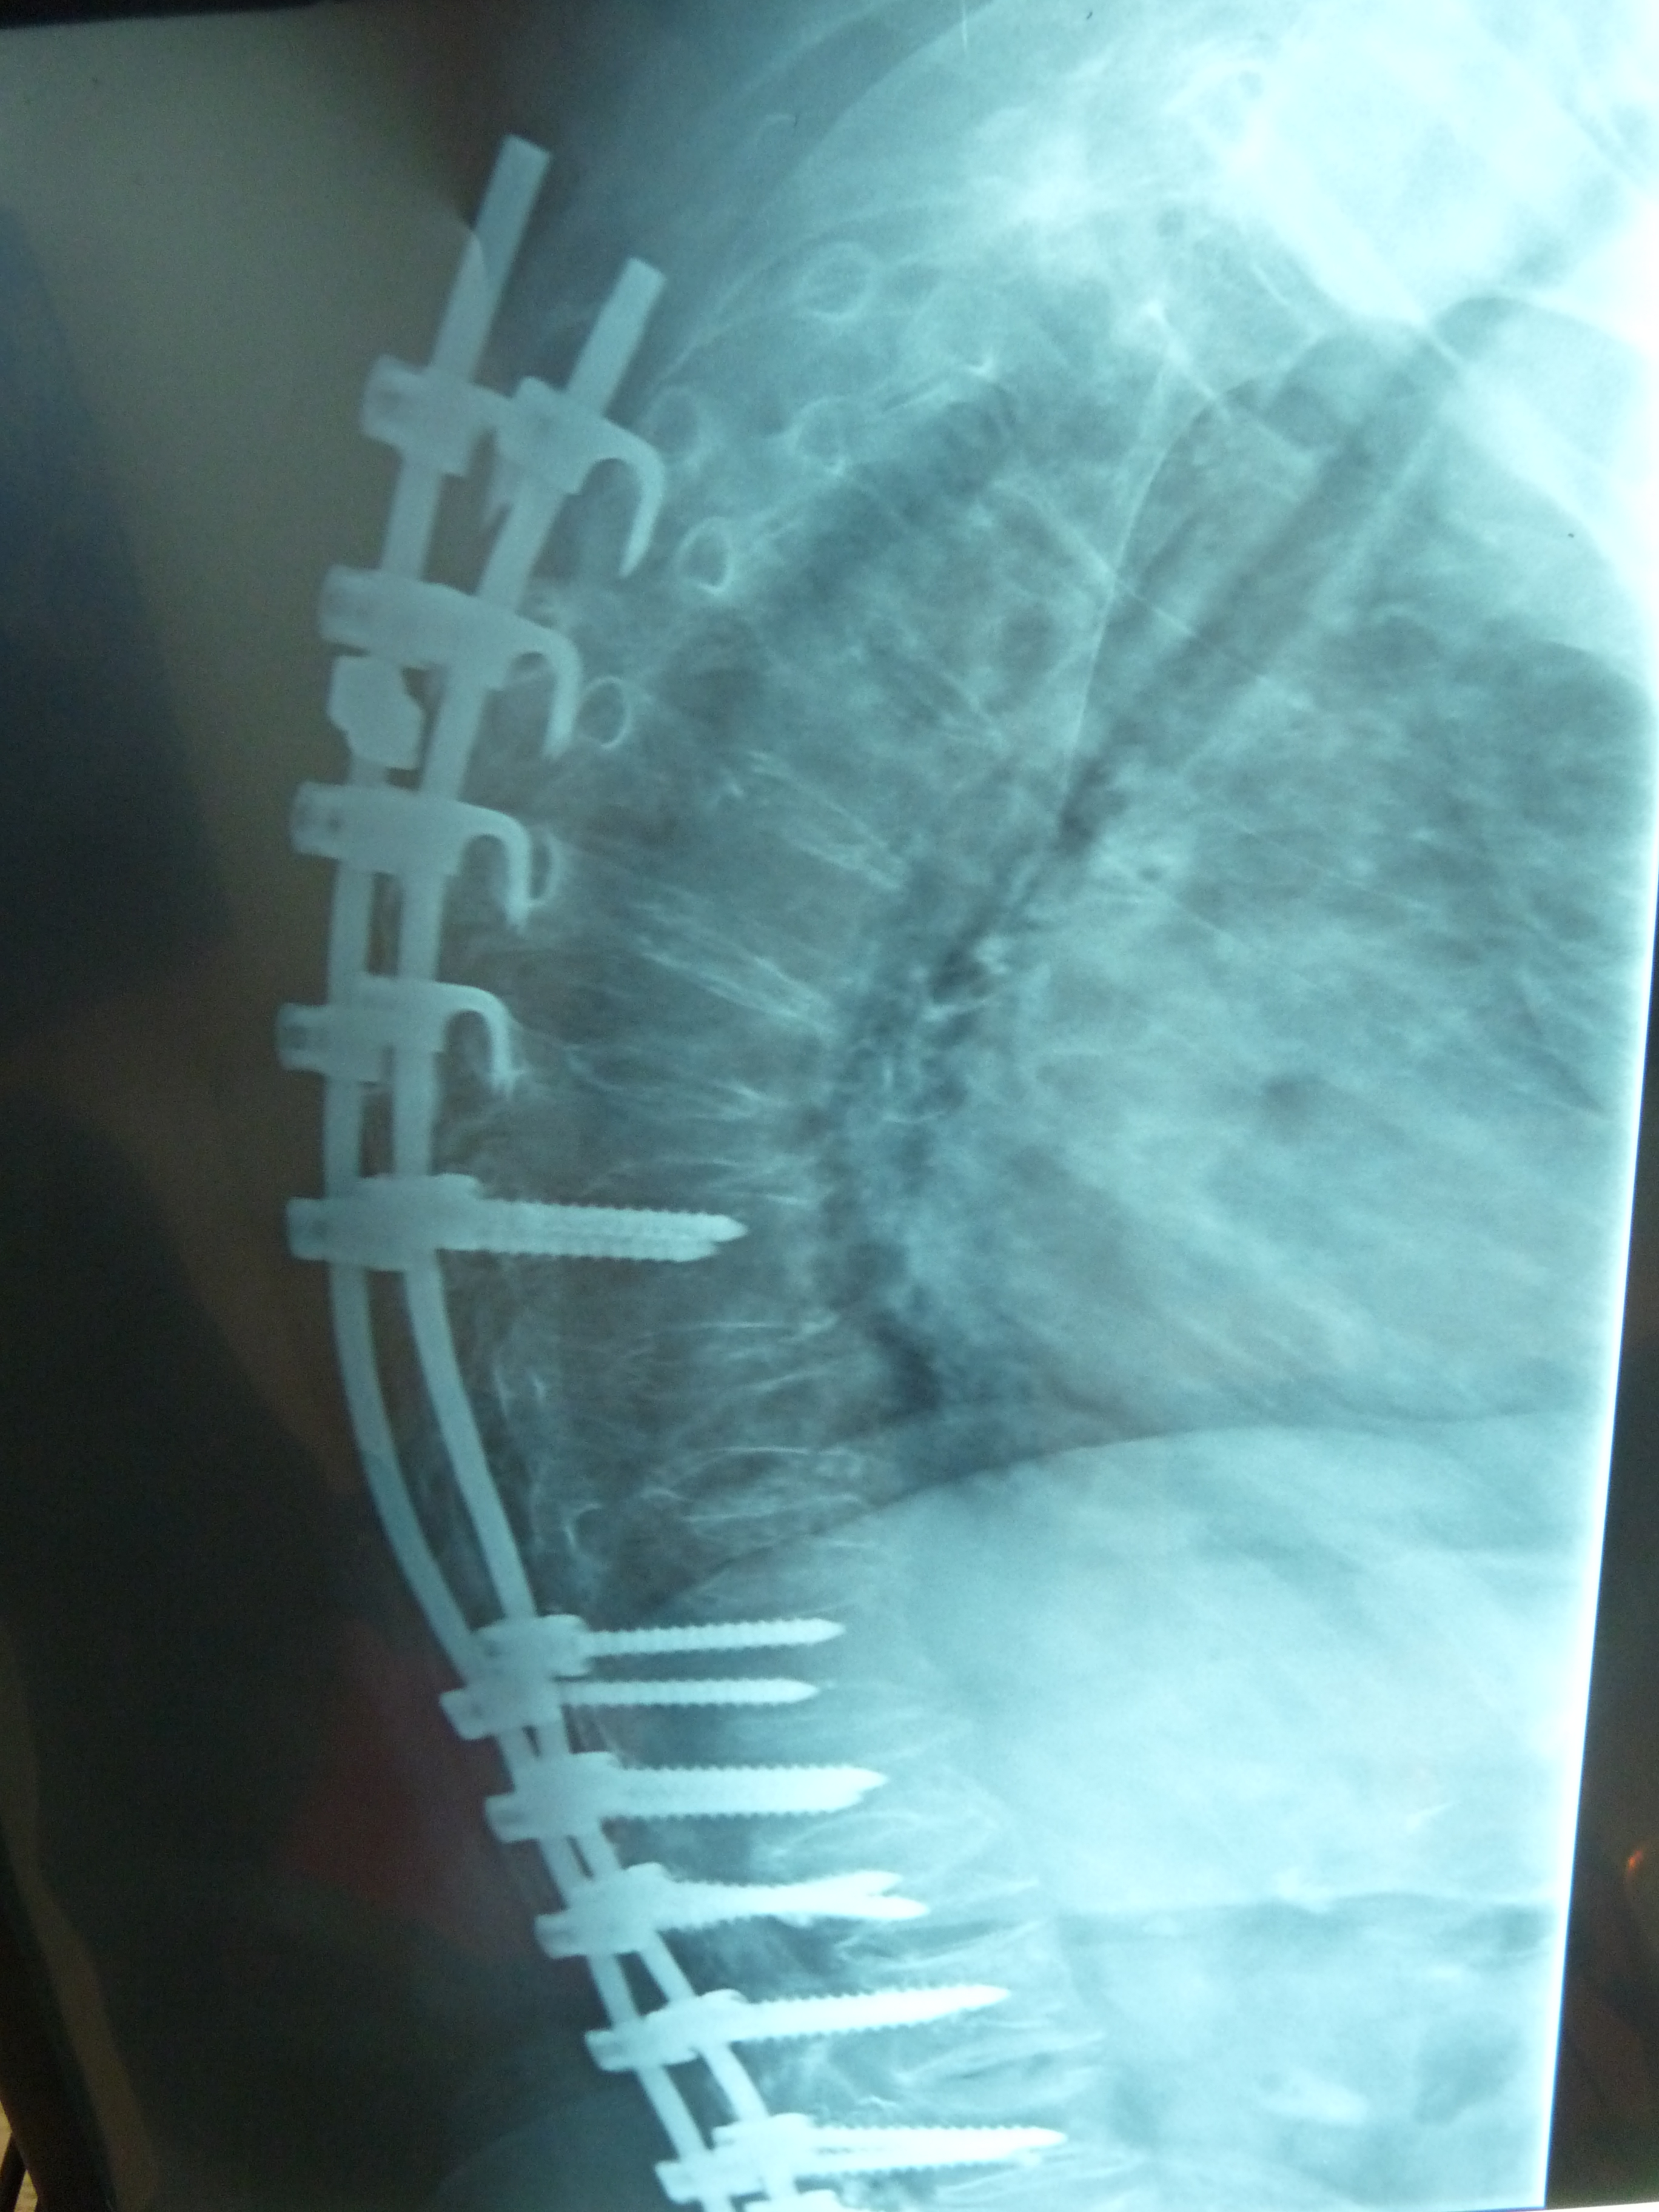

Εικόνα 3: α Προσθιοπισθία και β Πλαγία ακτινογραφία της σπονδυλικής στήλης

Η διόρθωση έχει πραγματοποιηθεί με εφαρμογή συστήματος σπονδυλοδεσίας (Διαυχενικοί κοχλίες και ράβδοι). Είναι εμφανής η διόρθωση της σκολιωτικής και κυφωτικής παραμόρφωσης της σπονδυλικής στήλης.

Η μετεγχειριτική πορεία υπήρξε πολύ καλή και η διόρθωση διατηρήθηκε στα επόμενα χρόνια.